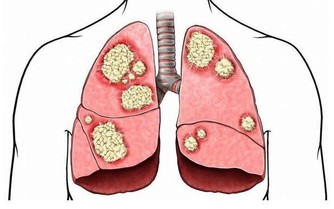

***三、痛風患者。***蝦屬於高嘌呤食物,容易加劇痛風症狀。